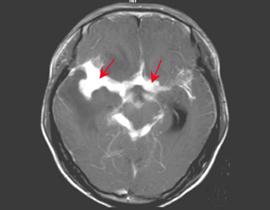

血常规检查大多正常,部分患者血沉可增高,伴有抗利尿激素异常分泌综合征的患者可出现低钠和低氯血症。约半数患者皮肤结核菌素试验阳性或胸部X线片可见活动性或陈旧性结核感染证据。CSF压力增高可达400mmH2O或以上,外观无包透明或微黄,静置后可有薄膜形成;淋巴细胞显著增多,常为(50~500)×106/l.蛋白增高,通常为1~2g/L,糖及氯化物下降,典型CSF改变可高度提示诊断。CSF抗酸染色仅少数为阳性,CSF培养出结核菌可确诊,但需大量脑脊液和数周时间北京张博士医考搜集整理。CT可显示基底池和皮质脑膜对比增强和脑积水。